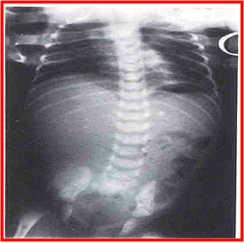

腹部平片:

十二指肠闭锁--双泡征(Double bubble sign)

空肠高位闭锁--三泡征

小肠低位闭锁--多数液平面